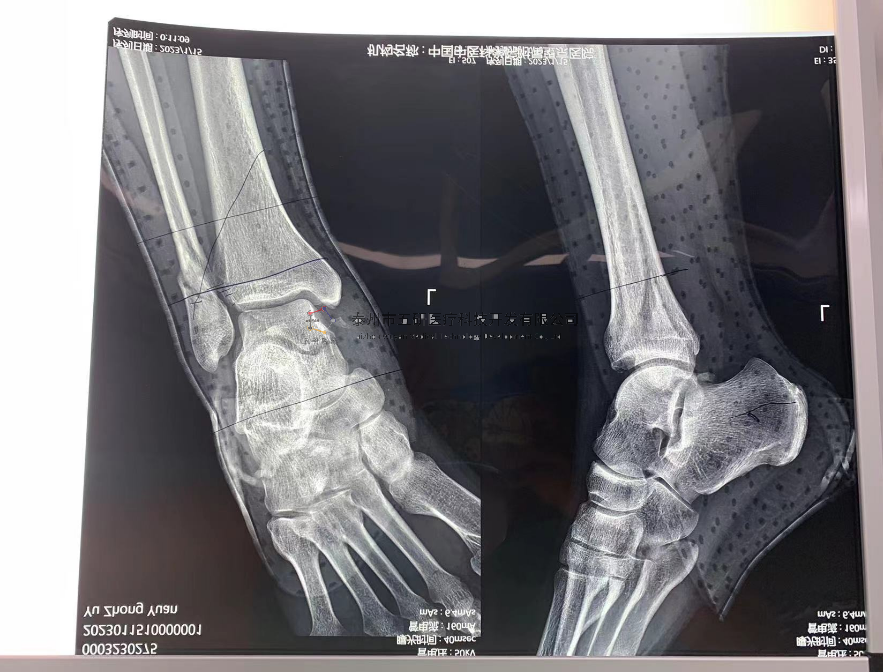

2

// 踝關(guān)節(jié)

本病例由中國(guó)中醫(yī)科學(xué)院望京醫(yī)院骨關(guān)二提供(術(shù)者:支架主任蔣主任)

【基本資料】患者,男,41歲

本病例踝關(guān)節(jié)骨折。手術(shù)名稱:左踝關(guān)節(jié)骨折外固定支架手術(shù)

【治療前影像】

4.png

5.png

【治療后影像】

6.png

7.png